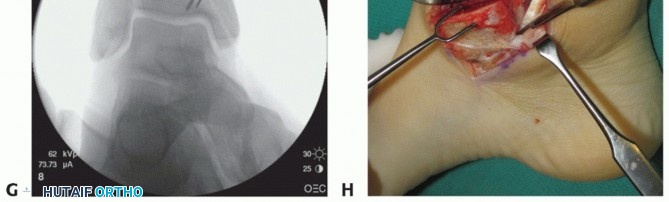

Using fluoroscopy, confirm that the graft and hardware are in optimal position (TECH FIG 4F-H).

The graft will not look perfect fluoroscopically, but as long as the clinical appearance is acceptable, the outcome has a good chance to be favorable.

The hardware may appear slightly proud fluoroscopically despite being countersunk. The talar dome is not a flat plane, and therefore the screw may seem to be protruding. Moreover, the articular cartilage is rather thick compared to such a low-profile screw head.

- TECH FIG 4 • A-C. Fitting and securing the graft to the native talus. A. After contouring the graft (some minor discoloration from debris while manipulating graft on back table; it is easily washed away). B. Drill hole perpendicular to graft. C. Securing graft with two countersunk screws. (continued)

- TECH FIG 4 • (continued) D,E. A different patient with similar graft, excellent interference fit, and secured with a single screw. D. Screw is inserted in lag fashion. E. Screw head is countersunk. F-H. Reduction of the medial malleolar osteotomy. F. Screw fixation through the predrilled holes. G. Antiglide plate. H. Final fluoroscopic evaluation of graft and reduction of medial malleolar osteotomy. Despite optimal clinical fit of the graft, rarely does the fluoroscopic appearance suggest anatomic graft match to the native talus, typically due to differing cartilage thicknesses between the donor and the host. Although the screws may appear prominent, two-dimensional fluoroscopy is deceiving because the screws are countersunk below the articular surface of the graft and the talar dome is curved.

Place the two screws in the predrilled holes and tighten the screws.

Although not essential for healing, we favor placing an antiglide plate over the proximal aspect of the osteotomy.

Using fluoroscopy, confirm reduction of the graft and medial malleolus (see TECH FIG 4).

Anticipate some incongruencies of the graft-native talus bony interfaces. It is difficult to achieve perfectly congruent apposition.

There will be a slight gap at the medial malleolar osteotomy site despite anatomic reduction of the medial malleolus. This is due to the thickness of the saw blade. However, it is not acceptable to see a step-off at the osteotomy site where it enters the tibial plafond; this must be anatomic.

The slight gaps at the graft and medial malleolus do not typically impair healing and should obliterate with eventual remodeling.